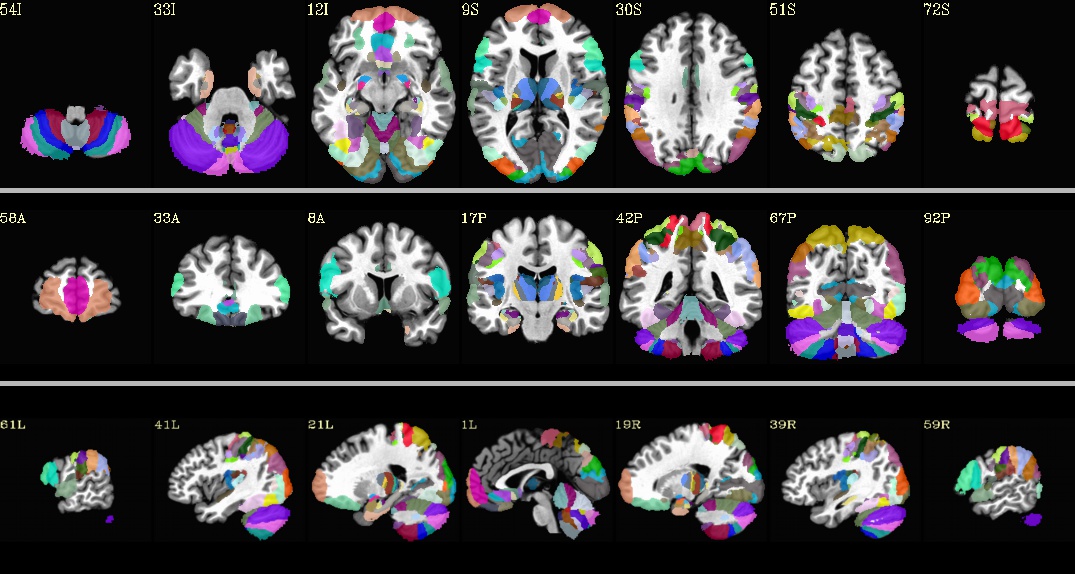

Julich_MNI2009c.nii.gz¶

Underlay: MNI152_2009_template_SSW.nii.gz |

Julich_MNI_N27.nii.gz¶

Underlay: MNI_caez_N27+tlrc.HEAD |